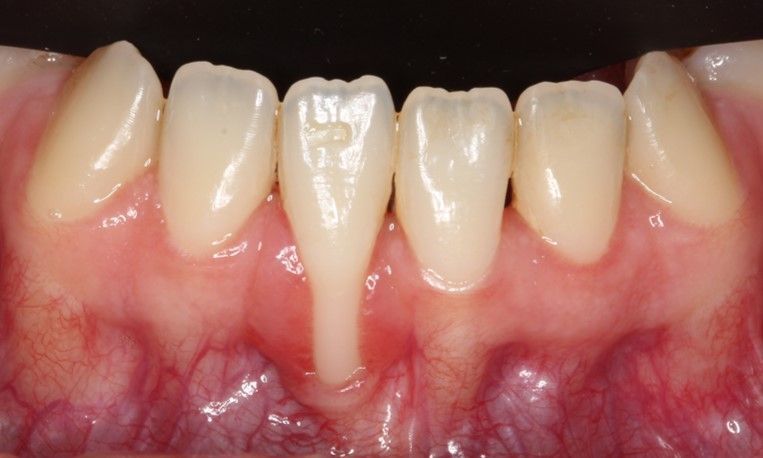

Gum recession can result from overzealous toothbrushing or orthodontic tooth movement out of the arch. Gum recession can compromise the appearance of the smile and can often result in the tooth being hypersensitive.

Gum recession can be repaired by undertaking gum plastic surgery. Taking a gum graft from the palate and surgically positioning it in the gum defect area. This is a very technique sensitive procedure undertaken by specialist periodontists.

Case 1